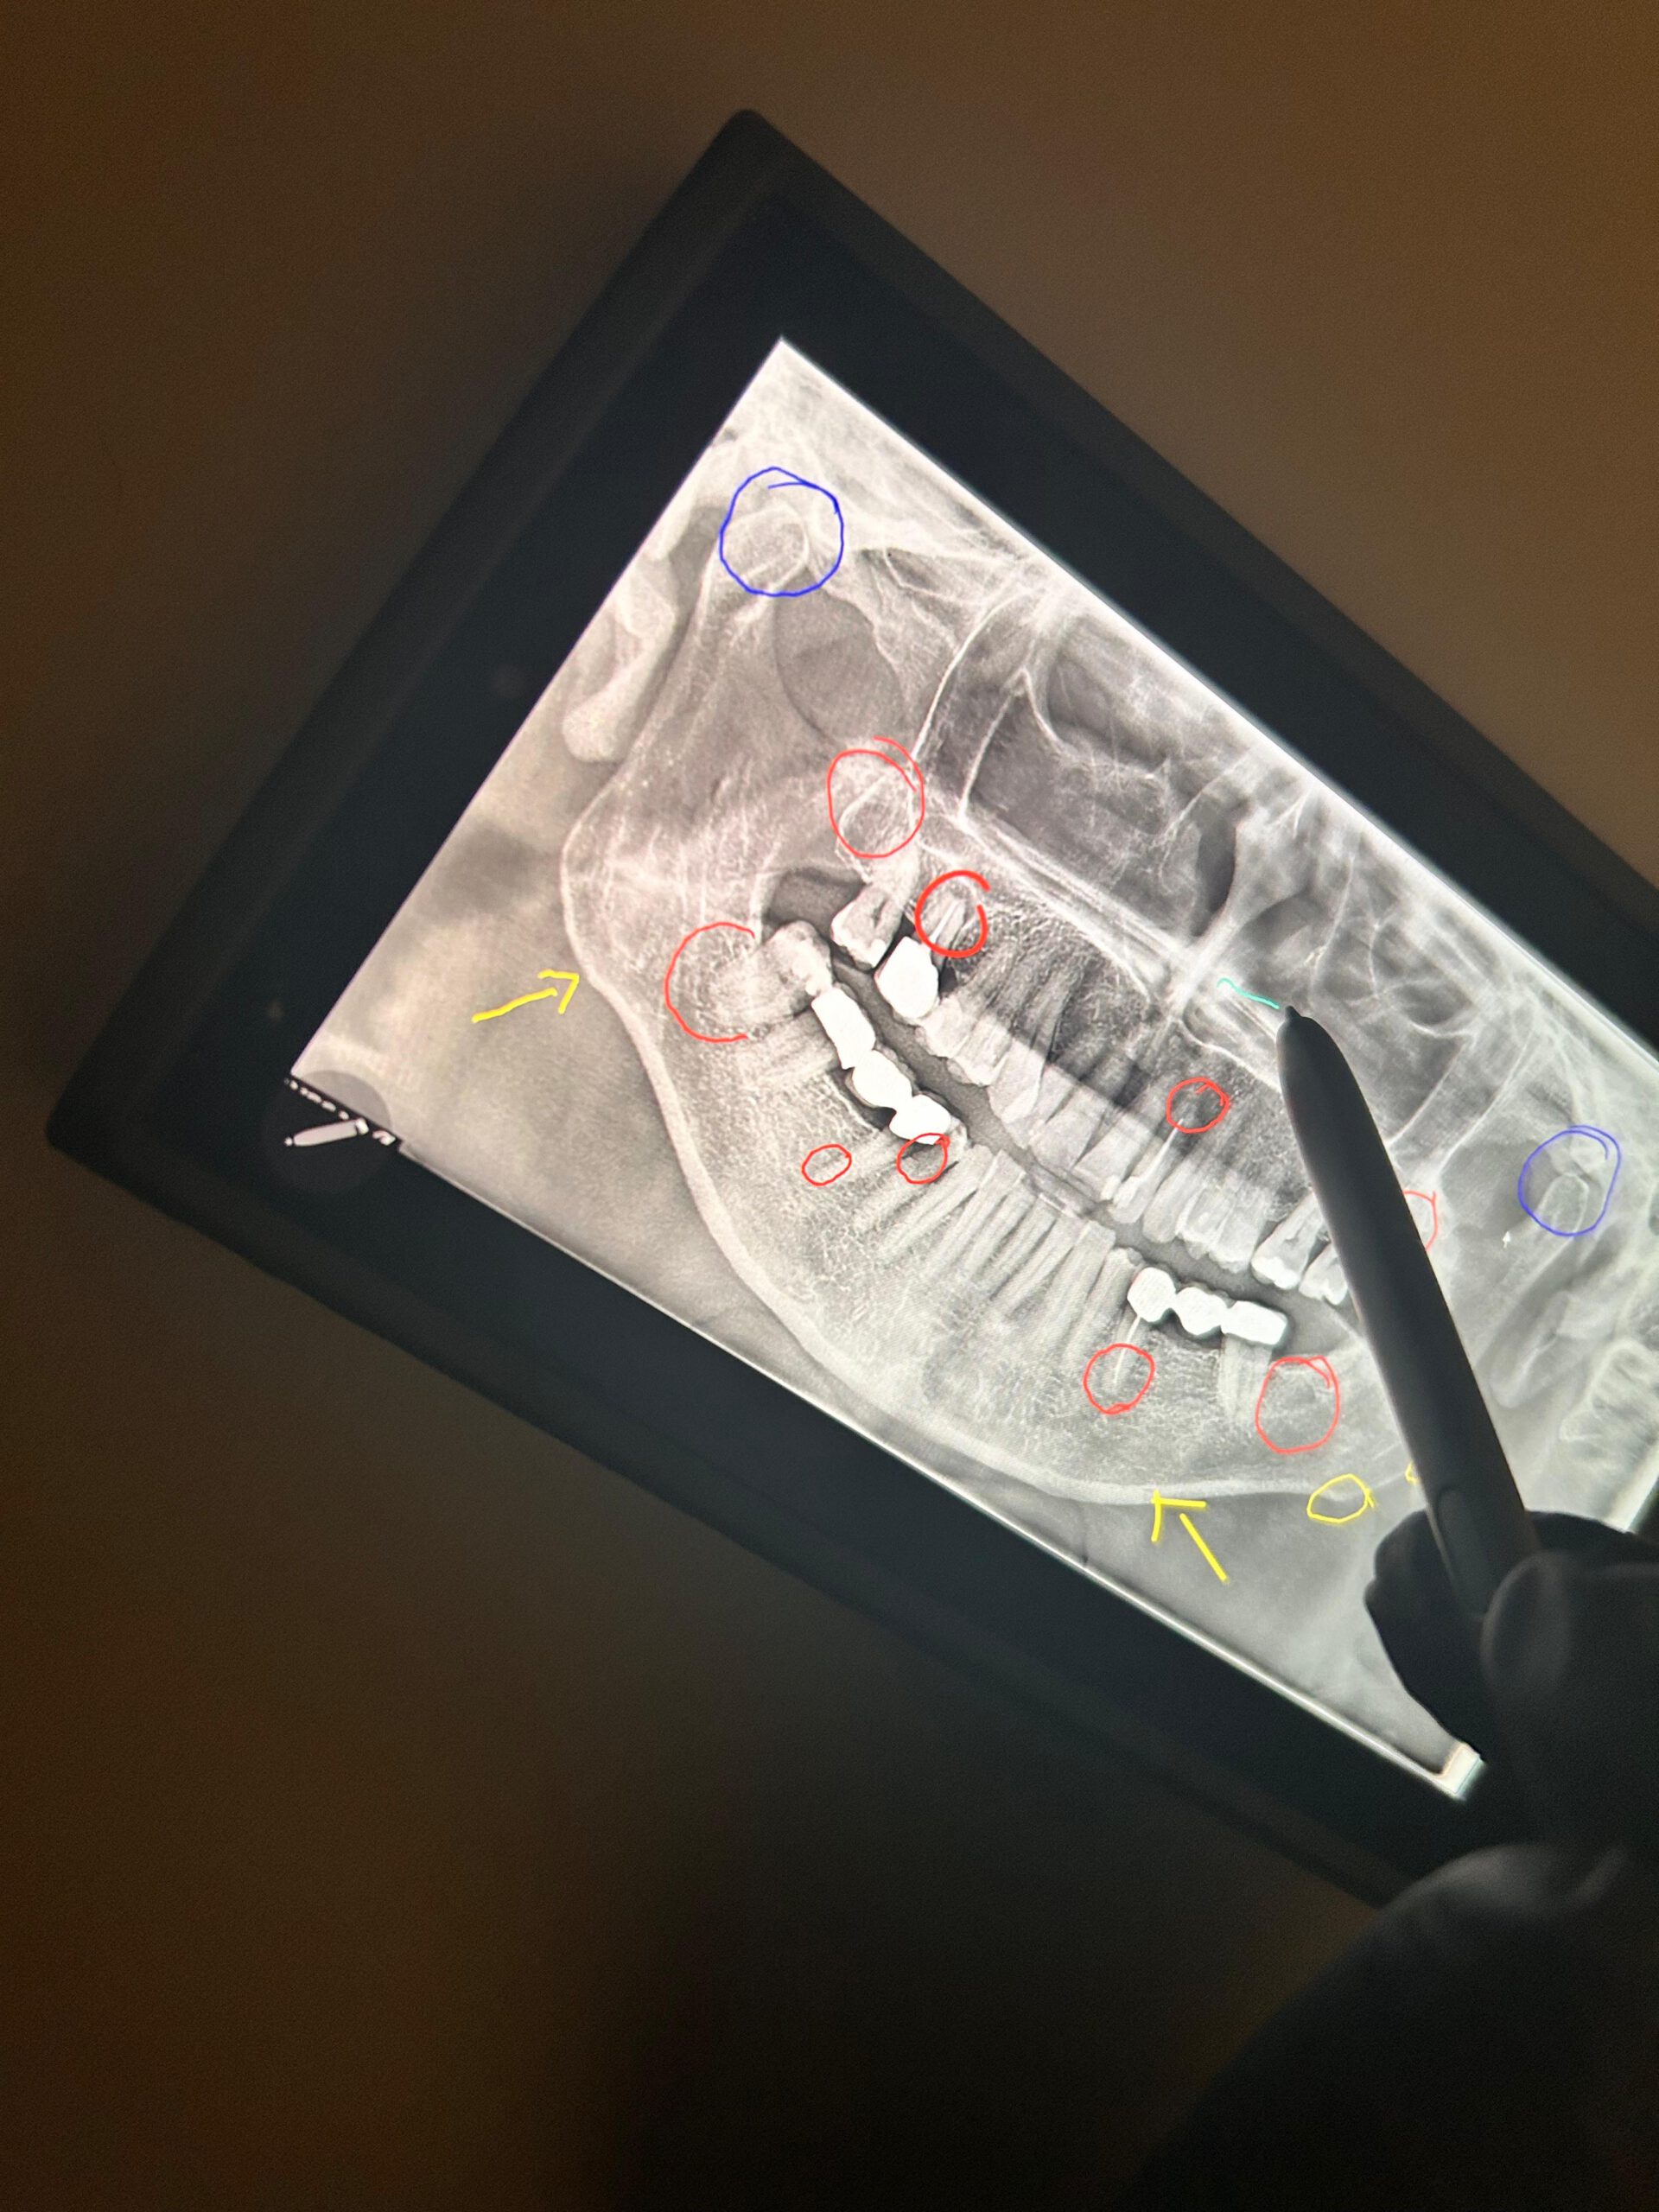

Die ganzheitliche Beurteilung von Panoramaaufnahmen (OPG) ermöglicht einen vernetzten Blick auf die Mundgesundheit – nicht nur auf einzelne Zähne, sondern auf die Zusammenhänge zwischen Zahn-Kiefer-Funktion, Immunsystem und Regulationsfähigkeit des gesamten Organismus.

Die ganzheitliche Betrachtung der Panoramaaufnahme (OPG) geht weit über die rein zahnmedizinische Diagnostik hinaus.

Sie ermöglicht es, komplexe Wechselwirkungen im gesamten Organismus sichtbar zu machen und aufzuzeigen, wie Zahn- und Kieferprobleme die allgemeine Gesundheit beeinflussen können.

Ein OPG ist mehr als nur eine Darstellung des Zahnstatus. Es kann Hinweise auf Zusammenhänge zwischen Zähnen, Organen, Hormonachsen und der Körperhaltung liefern.

Anhand der Zahnstruktur lassen sich zudem mögliche Hinweise auf Mikronährstoffmängel erkennen. Störfelder im Kieferbereich können hormonelle Dysbalancen, Verdauungsprobleme oder Schmerzen in anderen Körperregionen begünstigen.

Die integrale Betrachtung der Panoramaaufnahme unterstützt eine umfassendere Diagnostik, die frühzeitige Erkennung von Gesundheitsstörungen und die Entwicklung gezielter, individueller Therapiekonzepte.

Das OPG wird so zu einem Fenster in den gesamten Organismus.

Die ganzheitliche Betrachtung einer Panoramaaufnahme, die Patientinnen und Patienten zu ihrem Termin mitbringen können, ist ein wertvolles diagnostisches Werkzeug.

Sie ermöglicht einen 360°-Blick und dient als Grundlage für ein umfassendes integrales Gesamtkonzept zur Förderung der zahnmedizinischen und ganzheitlichen Gesundheit.